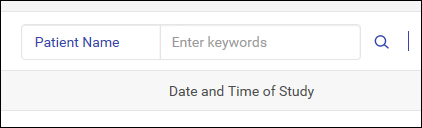

用户可以搜索患者以查找相关 DICOM 图像和相关信息。

搜索患者